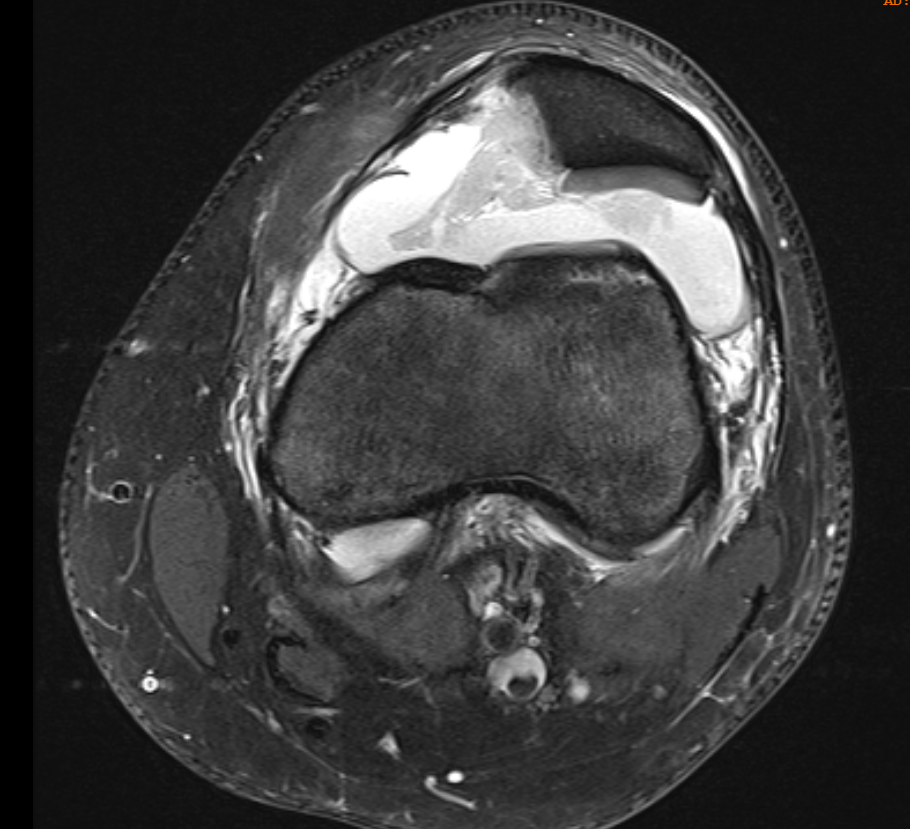

Osteochondral fracture lateral femoral condyle

MRI

Advantage

- identify smaller chondral lesions

- identify size of osteochondral fragment better than CT

- diagnose MPFL tear location